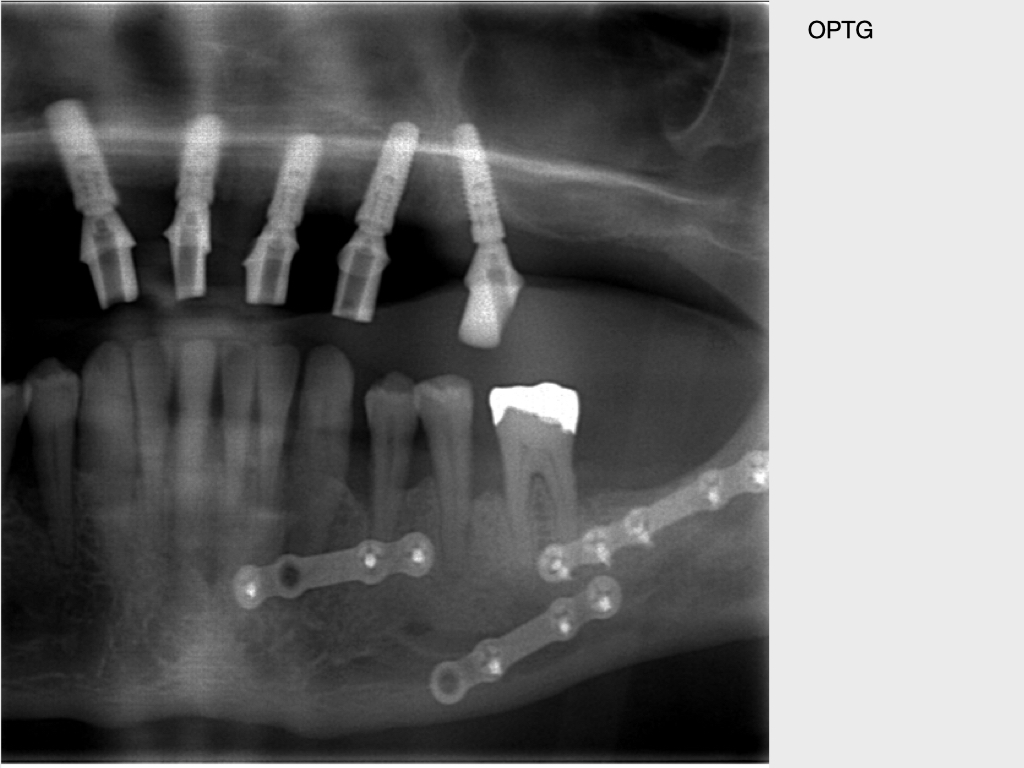

Submuköser Abszess 33